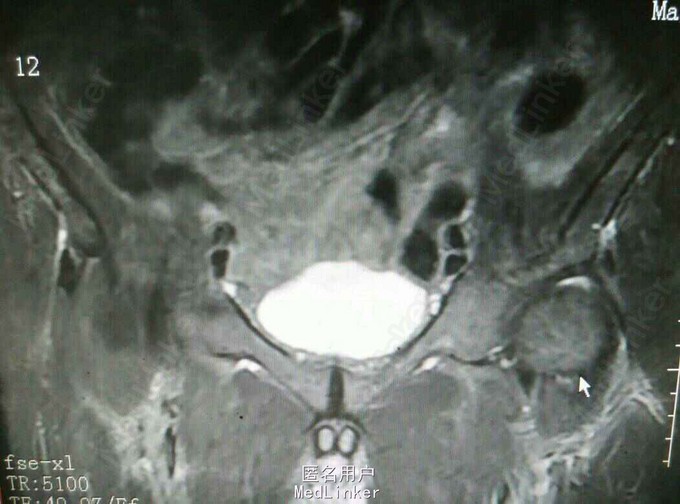

查体:腹部未及明显包块,四肢查体无异常,右臀部可及一5cm*3cm大小包块,质硬活动度差,边界不清。 复查:外院CT提示髂骨及骶骨翼骨质破坏,软组织肿块。 我院核磁提示髂骨骨质破坏软组织肿块,直肠距肛门1.5cm肠壁增厚肿块形成,考虑恶性肿瘤。 我院直肠镜检病理提示中分化腺癌

诊断:直肠癌 骨盆转移癌 治疗:建议我院肿瘤科专科治疗,患者拒绝,自动出院